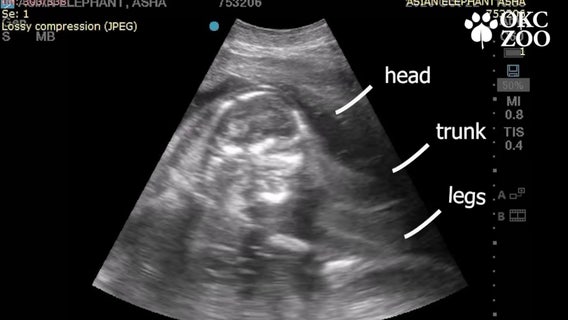

Oklahoma zoo shares ultrasound of baby elephant due in 2022

The elephant calf will be the fourth for 25-year-old Asian elephant Asha.